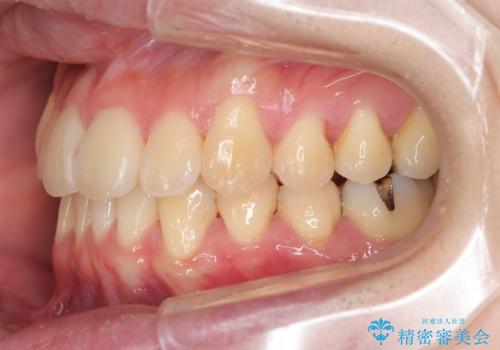

ねじれ・がたつきのある前歯を改善

- がたつき・すれ違い、ねじれのある前歯の見た目、噛み合わせの改善を希望され来院されました。

4本の小臼歯抜歯を避け、下顎前歯の1本抜歯の極力少ない抜歯本数で審美的な歯並びを得る治療計画としました。

すれ違いを治すのが得意な前歯部の部分ワイヤーを用いることで、治療期間を短縮することができました。